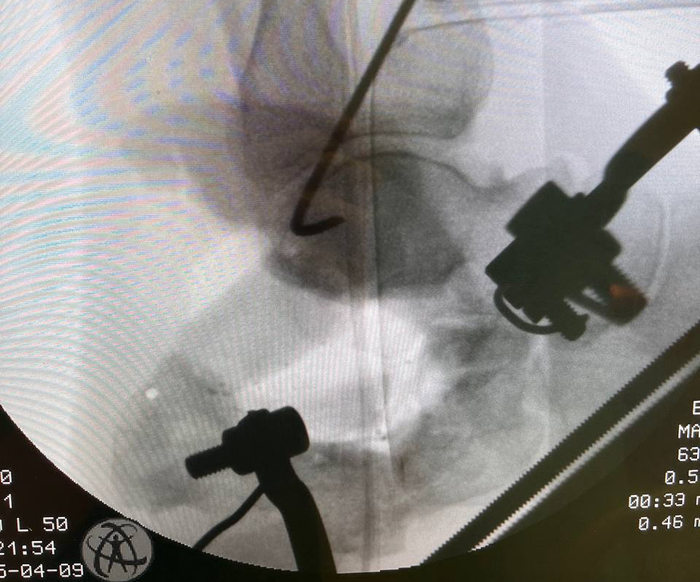

Всегда в начале операции выполняю прицелочный снимок, чтобы наглядно видеть с чего мы начинали.

Подобным образом выглядит ЭОП-снимок на этапе удаления металлоконструкции и склерозированной кости. Можно видеть силуэт дистрактора Хинтермана, который я использовал на данном этапе для временной дистракции подтаранного сустава, чтобы обеспечить лучшую визуализацию. Мы видим насколько уменьшился объем пяточной кости по сравнению с первоначальном этапом. Это результат резекции в пределах жизнеспособной кости. Жизнеспособность кости оцениваю исключительно макроскопически по наличию губчатой структуры и кровяной расы (да, под жгутом она тоже есть).

Этапный снимок с установкой аппарата.

ЭОП-контроль положения трансплантата. Можете обратить внимание, что окончательная дистракция больше чем была на промежуточных снимках.